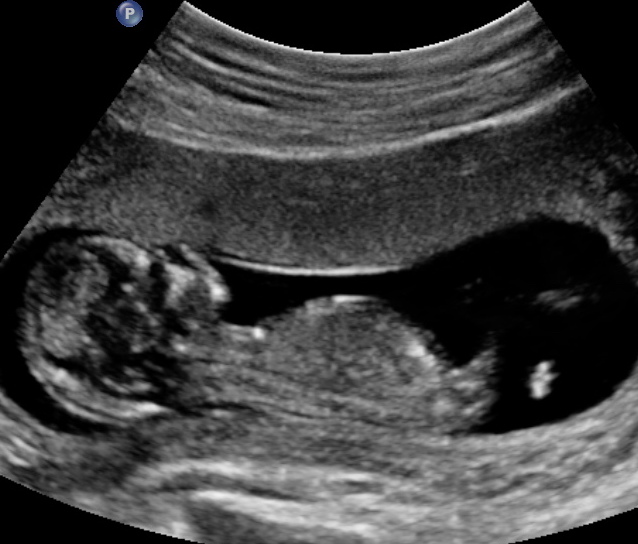

Attachment 37682

Getting a boy vibe, but really have no idea.